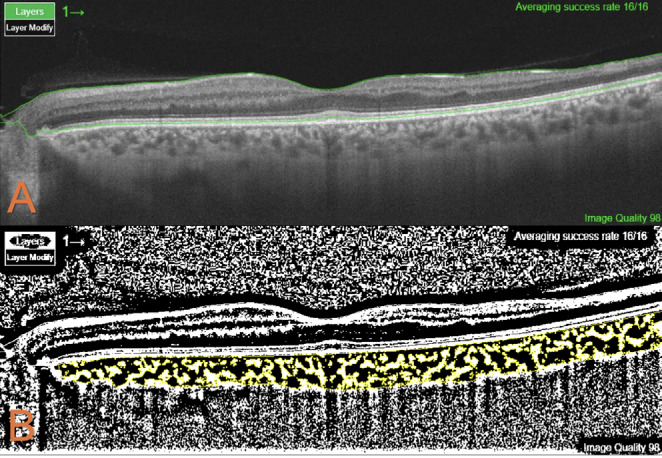

Materials and methods: In this cross-sectional study, 78 eyes of 39 patients with SCA were included in the patient group and 68 eyes of 34 healthy participants were included in the control group. Differences in foveal avascular zone (FAZ), retinal and subfoveal choroidal thickness (SFCT), and choroidal vascularity index (CVI) between the patient group and the control group were evaluated by swept source optical coherence tomography (OCT) and OCT angiography (OCTA) imaging. In addition, systemic and biological parameters were compared in patients with and without SCM.

Results: SCM was detected in 16 eyes of 8 patients. Proliferative sickle cell retinopathy (PSCR) was present in 10 patients. In logistic regression analysis, PSCR was found to be a risk factor for the development of SCM (p=0.015, odds ratio: 17.25, 95% confidence interval: 1.73-172.02). The temporal inner retinal layers were significantly thinner in the patient group compared to the control group. The patient group also exhibited significantly greater FAZ enlargement in both the superficial and deep capillary plexus when compared with the control group (p<0.001 for both). CVI was higher in the control group than in the patient group (p<0.001). SFCT was significantly thinner in the patient group (p=0.013). There was no significant difference between patients with and without SCM in terms of FAZ enlargement, CVI values, or systemic and biological factors.

Conclusion: In our study, PSCR was found to be a risk factor for the development of SCM. OCT and OCTA provide valuable information about microvascular changes in the retina and choroid in patients with SCM. Structural changes demonstrated by OCTA before the development of SCM are very important for follow-up and treatment in terms of visual prognosis of patients.